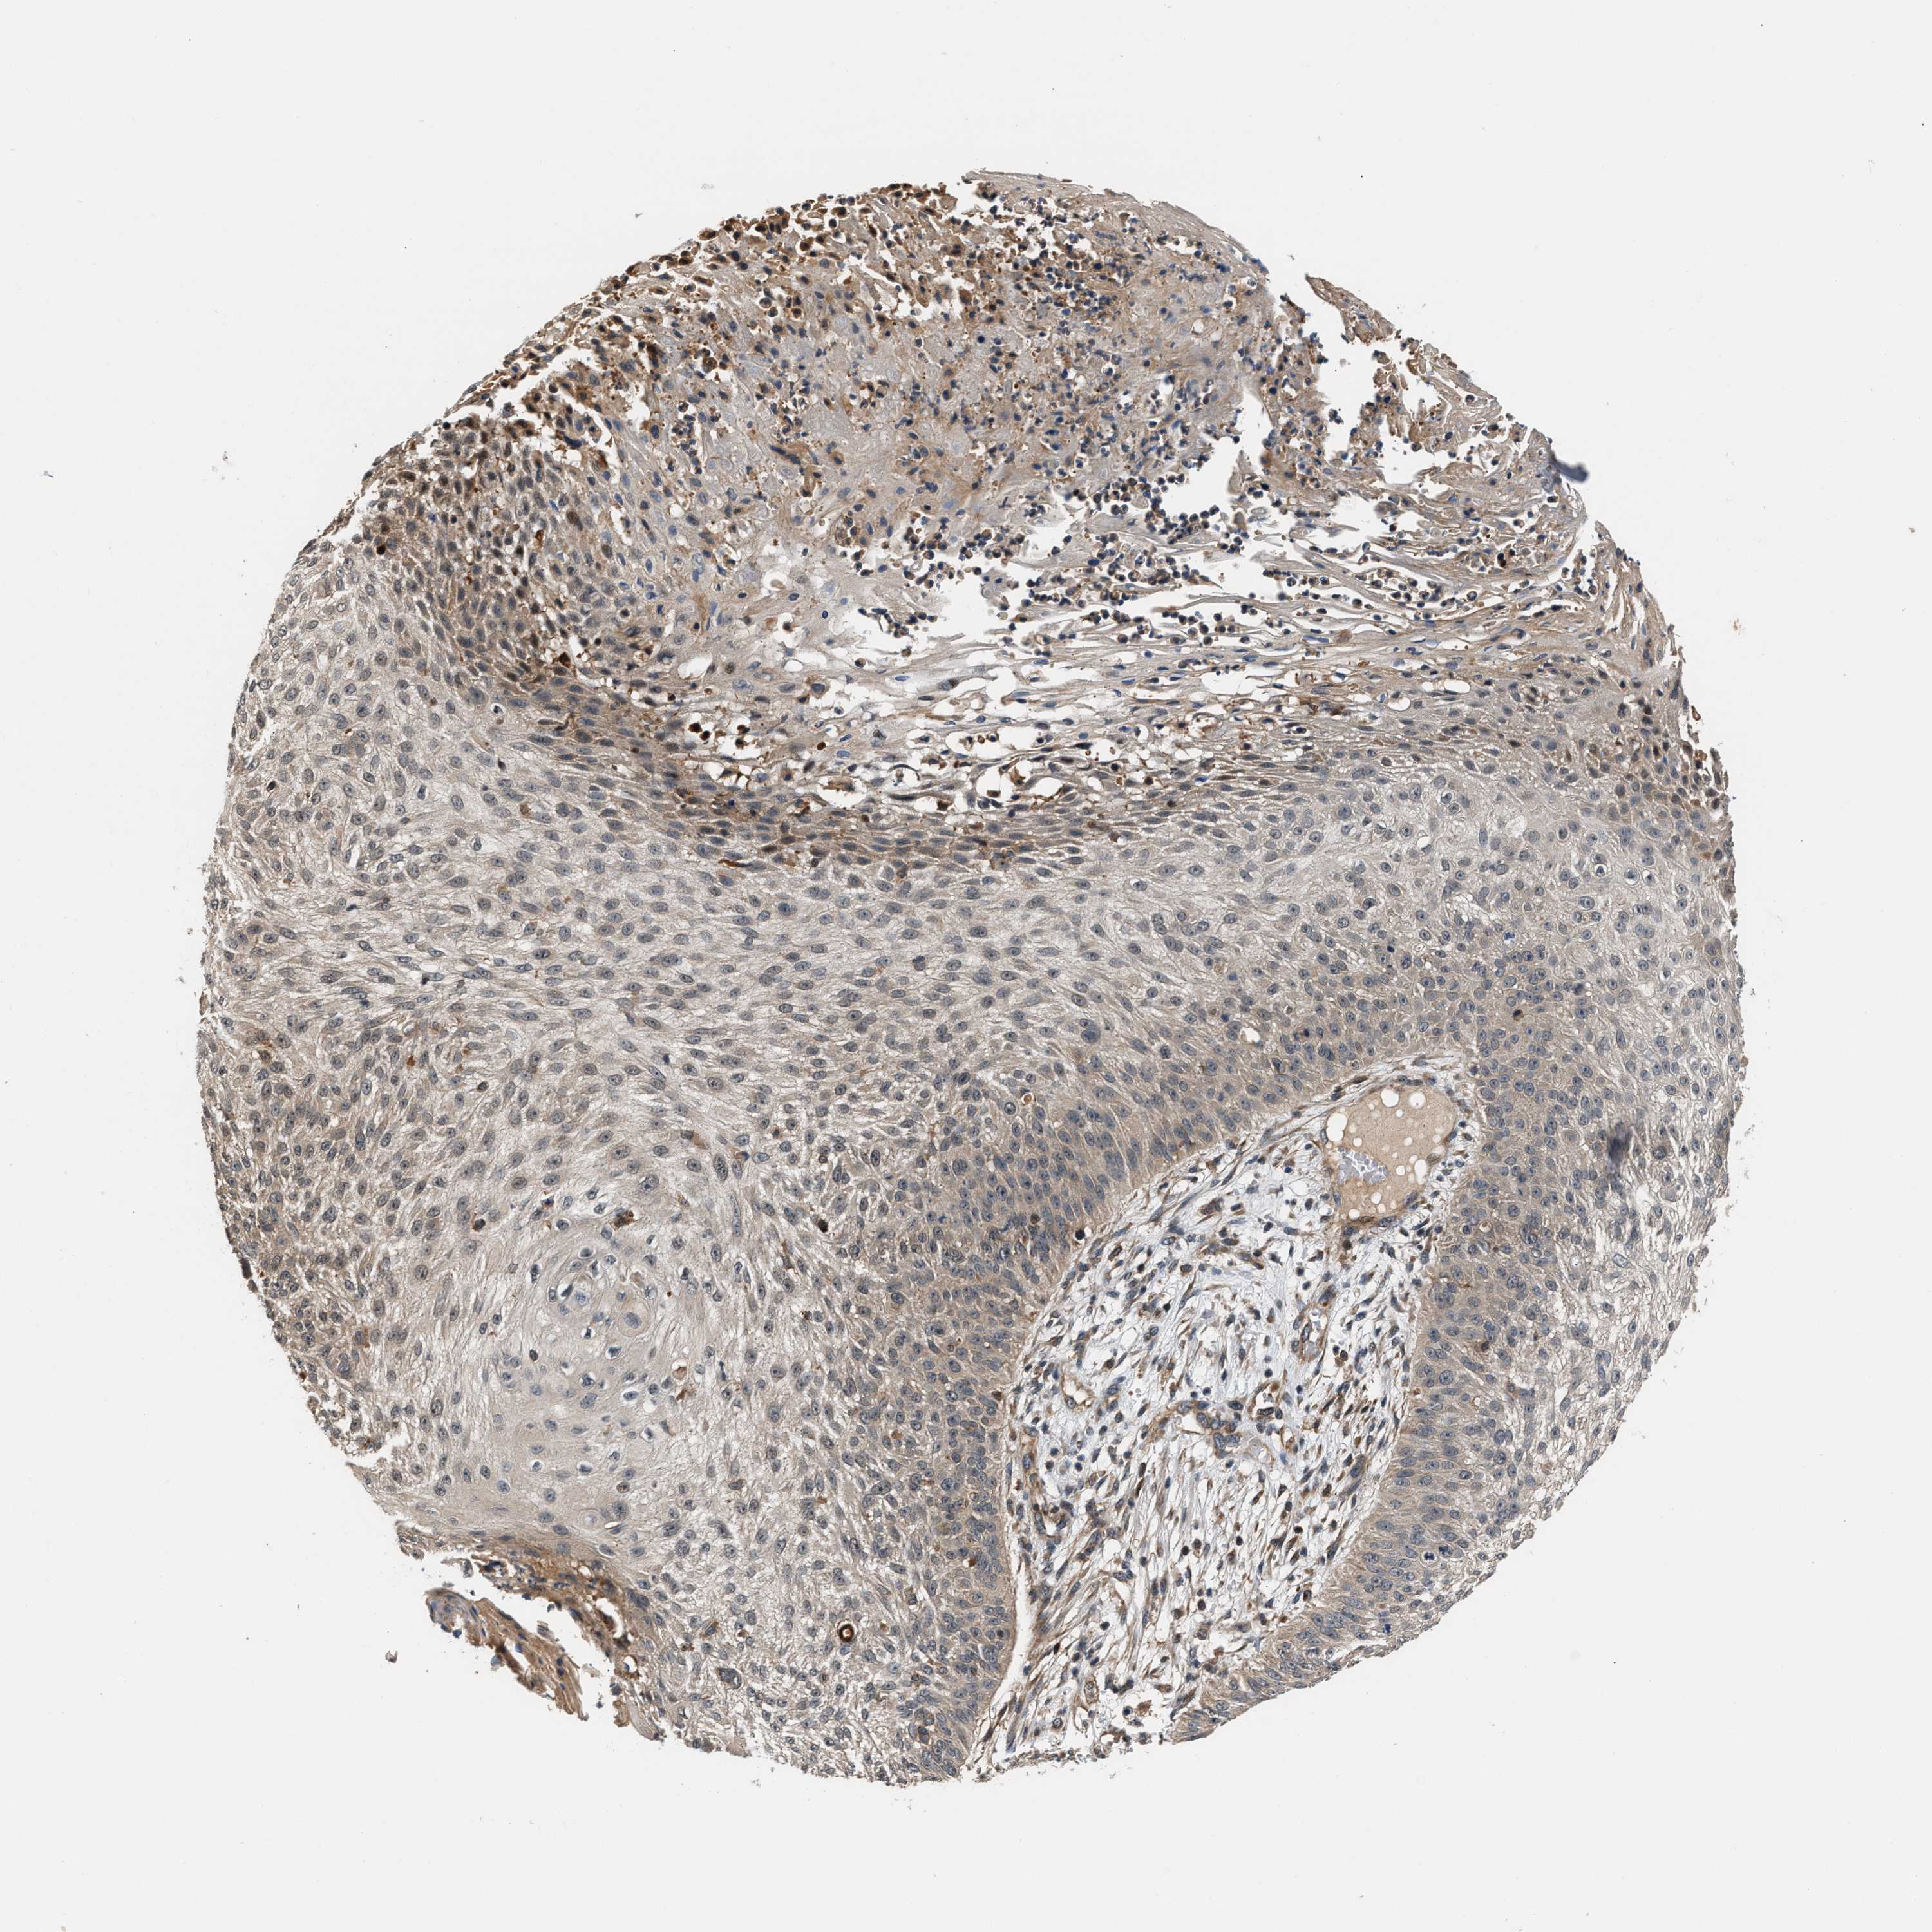

CANCER SKIN CANCER Show tissue menu

SKIN CANCER - Protein expressioni

A mouse-over function shows sample information and annotation data. Click on an image to view it in a full screen mode. Samples can be filtered based on level of antibody staining by selecting one or several of the following categories: high, medium, low and not detected. The assay and annotation is described here.

Each image is clickable and will lead to virtual microscopy that enables deeper exploration of all samples and also displays staining intensity scores, fraction scores and subcellular localization as well as patient and tissue information for each sample.

Antibody HPA020615

Squamous cell carcinoma in situ, NOS

Squamous cell carcinoma, NOS

Squamous cell carcinoma, metastatic, NOS

Basal cell carcinoma